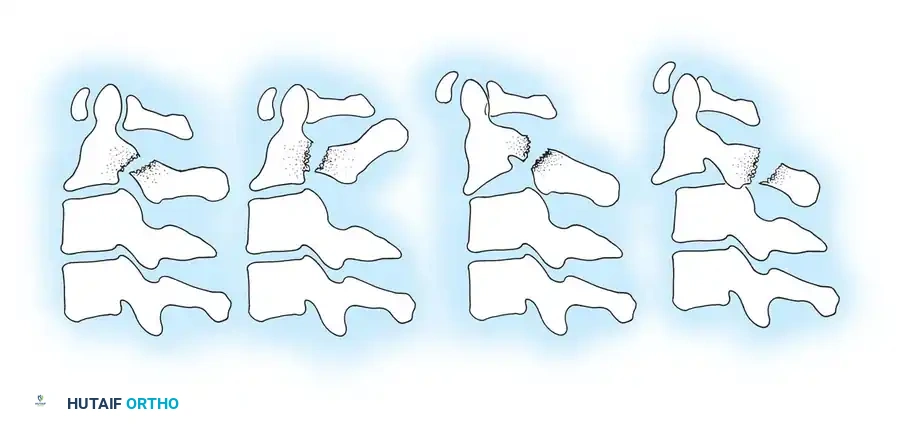

While numerous classifications of cervical spine injuries have been formulated over the decades, the mechanistic classification proposed by Allen et al. remains one of the most comprehensive and clinically useful frameworks. Based on a rigorous review of 165 lower cervical spine injuries, Allen and colleagues identified six common patterns of injury. Each pattern is subdivided into progressive stages based on the severity of failure in the osseous and ligamentous structures.

Compressive Flexion (Five Stages)

This injury pattern typically results from a force applied to the anterior cranium while the neck is in flexion.

* Stage 1: Blunting of the anterosuperior vertebral margin to a rounded contour. There is no evidence of failure of the posterior ligamentous complex (PLC).

* Stage 2: In addition to Stage 1 changes, there is obliquity of the anterior vertebral body with loss of anterior centrum height. The anteroinferior vertebral body develops a "beak" appearance, and a vertical fracture may be present.

* Stage 3: Features of Stage 2 plus a fracture line passing obliquely from the anterior surface through the centrum and extending through the inferior subchondral plate. The anterior "beak" is fractured.

* Stage 4: Deformation of the centrum and fracture of the beak with mild (< 3 mm) displacement of the inferoposterior vertebral margin into the spinal canal.

* Stage 5: Severe bony comminution with > 3 mm of posterior displacement of the vertebral body into the spinal canal. The vertebral arch remains intact, but the articular facets are separated, and the interspinous space is widened, indicating a catastrophic posterior ligamentous disruption in tension.

Vertical Compression (Three Stages)

Resulting from pure axial loading, often seen in shallow-water diving accidents.

* Stage 1: Fracture of the superior or inferior end plate with a central "cupping" deformity. The PLC remains intact.

* Stage 2: Fracture of both vertebral end plates with cupping deformities. Minimal displacement is observed despite centrum fracture lines.

* Stage 3: Severe fragmentation of the centrum with peripheral displacement in multiple directions (burst fracture). The posterior aspect of the vertebral body is often retropulsed into the spinal canal. The PLC may fail depending on the degree of comminution.